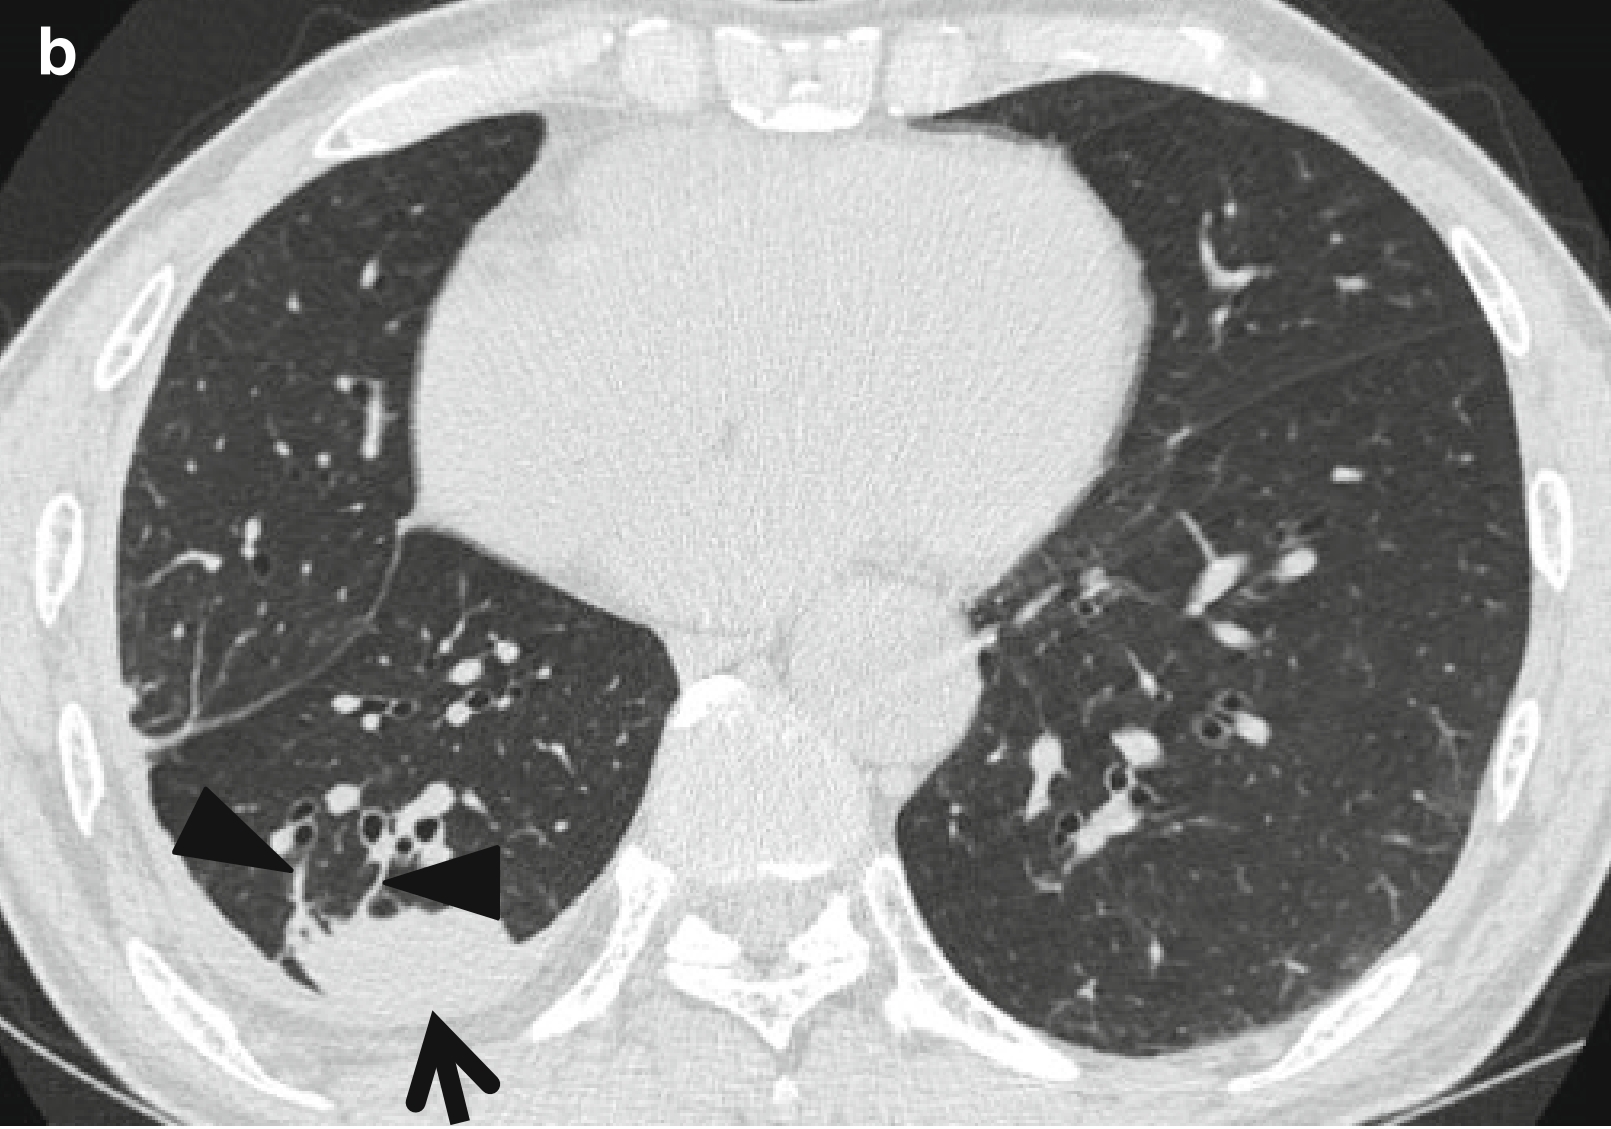

图1 圆形肺不张。

男,66岁,主诉气促和咳嗽。

(a,b)连续薄层 CT(层厚=1.5 mm)扫描于心室水平示右肺下叶(箭头所示)胸膜下圆形肺不张,并可见两条迁曲血管样的条索状软组织密度影(楔形箭头所示),由圆形肺不张的前缘延伸至肺门;这两种结构有助于理解降落伞征(参见彗尾征定义)。并且,可于不张肺组织的后方见胸腔积液和胸膜增厚,以及胸膜外肋骨下脂肪堆积。

(c)纵隔窗可见不张的肺组织强化(箭头所示)。